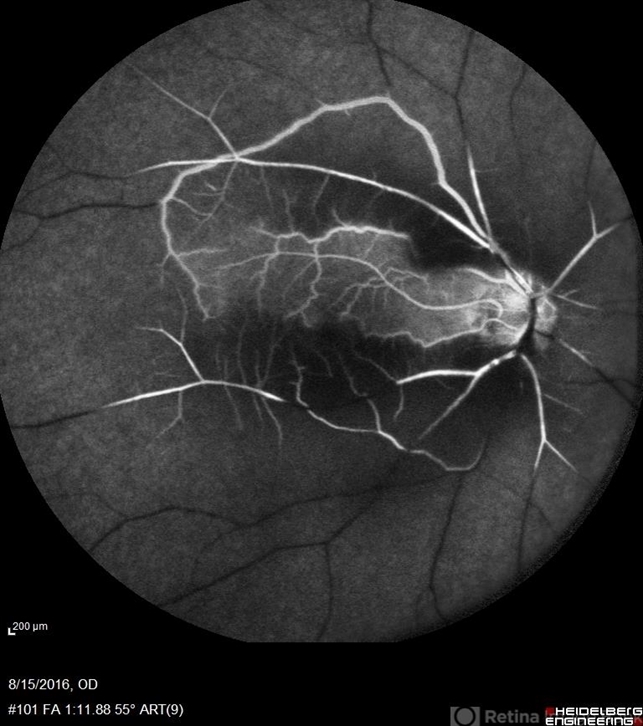

- central retinal artery occlusion (CRAO), cilioretinal artery, cilioretinal sparing

- 60-year-old female with sudden loss of vision of right eye.